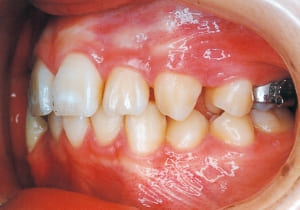

Age at initial visit : 7 y 7 m, male /Protruding upper bite. Open bite. Receding lower jaw. Protruding dual dentition.

1 Initial Visit 2-11-’88

3 Initial Visit 2-11-’88

4 Initial Visit 2-11-’88

The Class II condition is pronounced, with a significant overjet of 12.5 mm(3). Although the teeth size are large, crowding is relatively mild. The maxillofacial structure has good depth and a robust bone framework(5). The mandible itself is solid , robust gonial angle, but there is significant anterior-posterior displacement relative to the maxilla(ANB 10.0°). While there is no confirmed history of thumb-sucking or similar habits, the lower lip is already pushing up against the maxillary incisors. The cause of this condition is unknown.